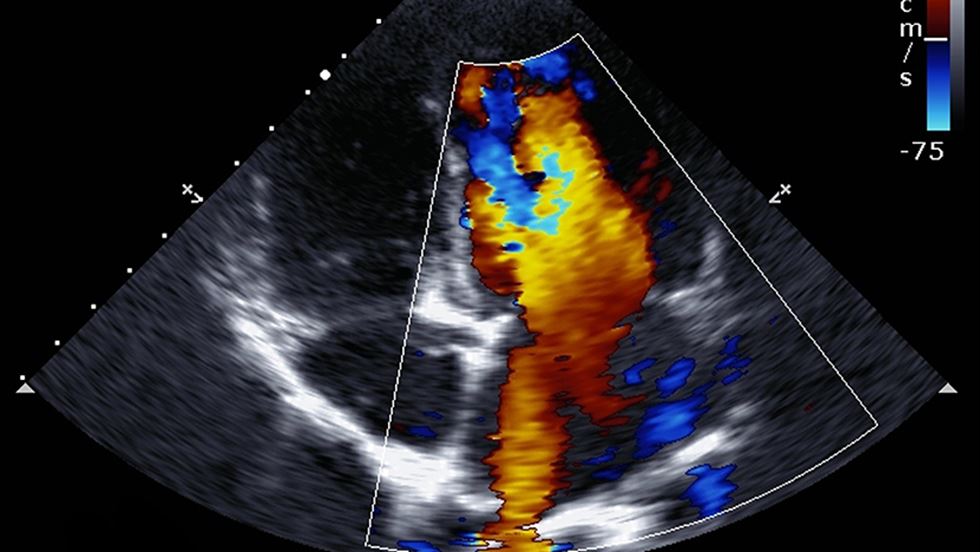

Videoarkiv

Länk till ett videoarkiv med ekokardiografiska bilder.